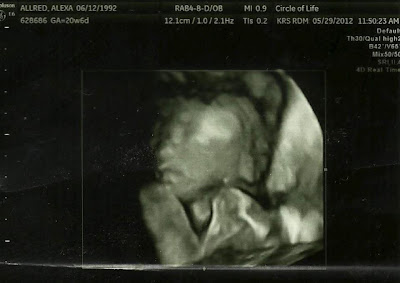

The ultrasound tech was also super fun! She was so nice and spent about a half hour with us and was super patient (Asher was being a brat again and wouldn't let us get very good pictures... imagine that! haa!) and gave our naughty little boy no other choice but to cooperate. We got some awesome 3D pictures of his cute little face and some more proof that we are definitely having a boy (that always makes Eric super proud haha!)

what a handsome little guy right??